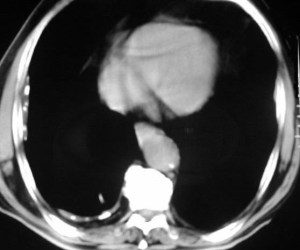

SIGNO DE LA ALMOHADILLA EPICÁRDICA (O SIGNO DE LA GALLETA OREO)

Signo de derrame pericárdico en la radiografía lateral de tórax. El derrame aparece como una banda curva de densidad agua que separa las capas grasas pericárdicas visceral y parietal a nivel retroesternal bajo.

La radiografía posteroanterior de tórax del mismo paciente muestra el aumento de tamaño de la sombra cardíaca con la morfología característica del derrame pericárdico (corazón en “tienda de campaña”). A la derecha, la imagen de TC con el derrame pericárdico (D) separando las capas grasas pericárdicas visceral (V) y parietal (P).

En la literatura en inglés, este signo es llamado «oreo cookie sign» por el aspecto de las capas hipo, hiper e hipodensa.